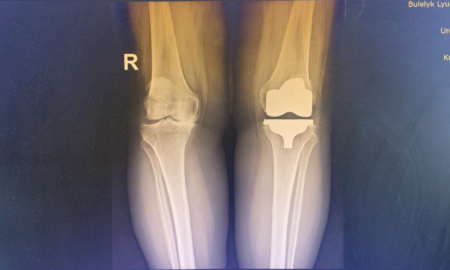

У відділенні ендопротезування Івано-Франківської обласної клінічної лікарні почали застосовувати кінематичне вирівнювання. Це новітній підхід до заміни колінного суглоба, який не так давно...